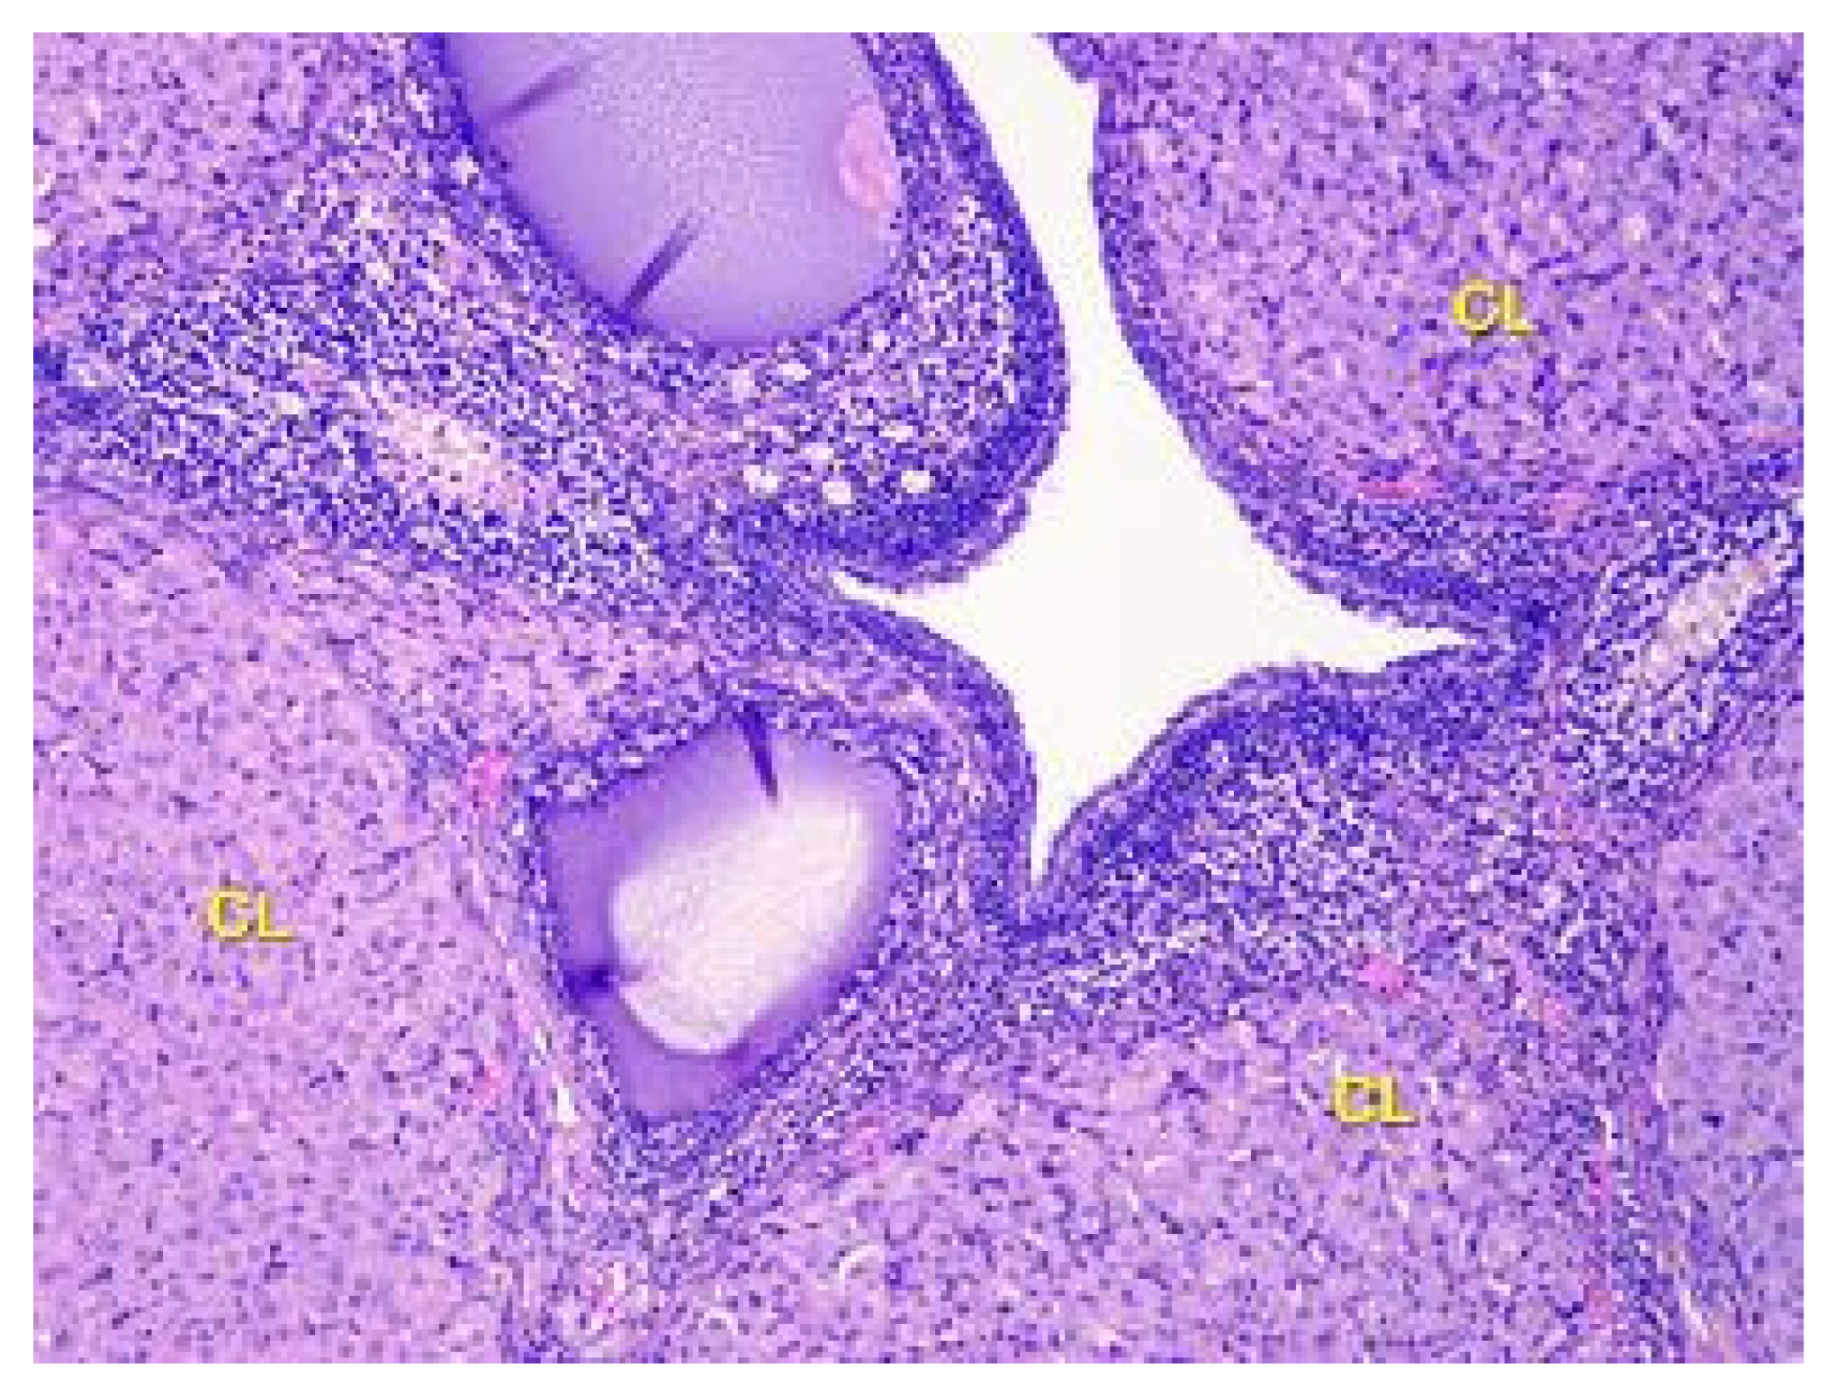

- Denefil, O.V.; Bilyk, Y.O.; Chorniy, S.V.; Fedoniuk, L.Y.; Chornii, N.V. The peculiarities of morpological changes of rats’ ovary and biochemical state under the damage with different doses of lead acetate. Wiad Lek. 2022, 75, 377–382. [Google Scholar] [CrossRef] [PubMed]